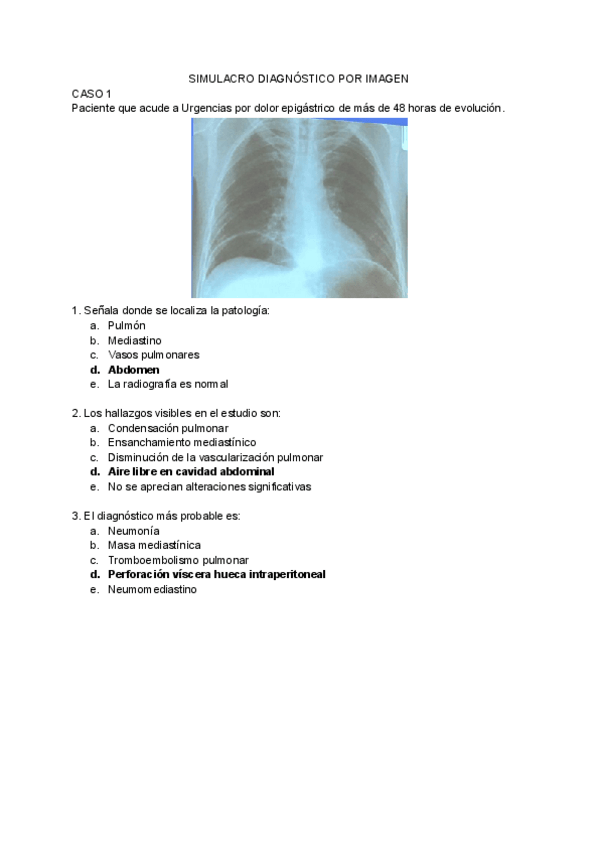

He publicado nuevos apuntes de 4º Diagnóstico Por Imagen: SIMULACRO-DIAGNOSTICO-POR-IMAGEN.pdf

6 páginas